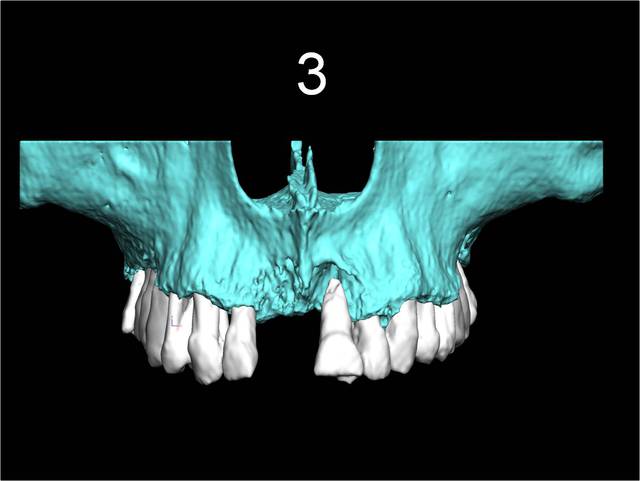

3

19/02/2013 à 14h36

Celui la est très moyen au niveau osseux

22 implants au total et pas une seule vis!

Pluton 2 max stab, tu vois cela m'arrive aussi d'en mettre!